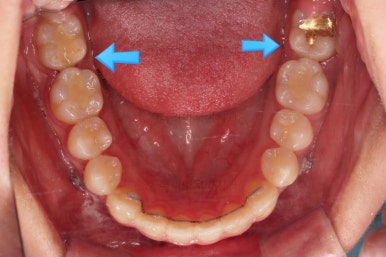

점점 뒤쪽 치아가 바로 일으켜 세워지고 있네요.

생각보다 많이 썩은 상태였어요.

앞쪽 치아 하방으로 갇혀 있으신 훨씬 심각한 상태까지 충치가 진행되었던거죠.

전후사진을 비교해볼게요.

약간의 주걱턱, 돌출입은 고칠 의사가 없어서 그대로 유지하였고 주걱턱 패턴으로 인한 부정교합 부분을 개선했으며 무엇보다 중요한 것은 쓰러져서 많이 썩어있던 치아를 자칫 치료 못할 뻔 했는데 교정치료와 병행하여 훌륭하게 치료하여 살려 썼다는 점이었어요.